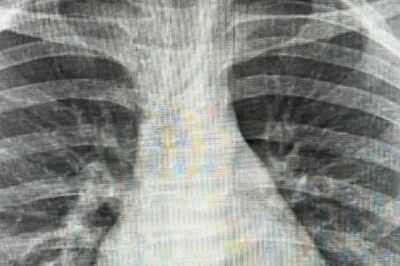

Despite being warned about putting things in his mouth, Michael – who has autism and ADHD – would often chew different items due to sensory issues. Holly took her son to hospital, but an X-ray of his lungs didn’t show the ring pull.

However, when Michael kept wheezing, she took to TikTokto ask for advice, where other parents informed her that ring pulls only appear on a certain type of X-ray. Holly told Belfast Live that she then called an ambulance, but was told yet again in A&E that there was no ring pull in her son’s lungs.

Holly went away to do her own research and found an article in the British Medical Journal that said a ring pull wouldn’t show up on a standard X-ray “because of the density”. When Holly took Michael back to A&E, she was adamant that the experts listen. A consultant went to X-ray a ring pull to test out her theory and came back to tell the mum that she was right.

She said: “He went and X-rayed a ring pull from a can then said to me 'you've taught us all something, because it doesn't show up.'” It was at this point that the ring pull was finally removed.